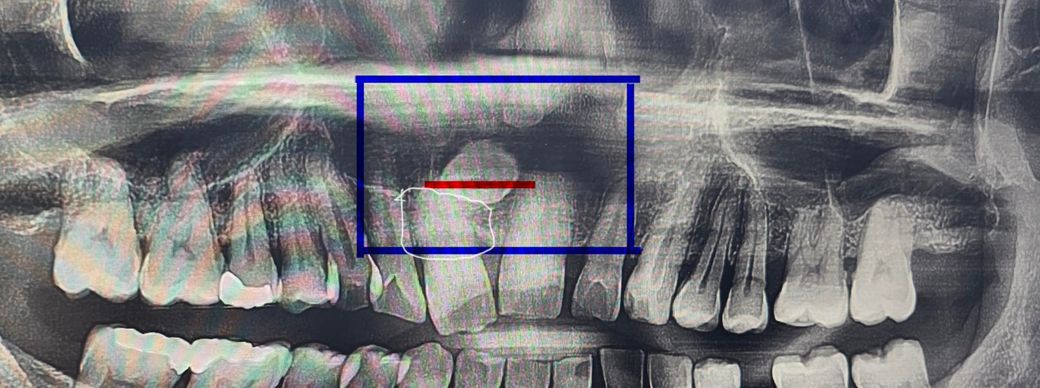

사진상에 보이는 가로로 빨간색 부분이 개봉했던 자리이고,

흰색 네모칸이 부분이 감각이 없는 부분입니다

해당부위를 누르면 마취된 상태의 느낌이며,손으로 누르면 누르는 압력은 살짝 느껴집니다.